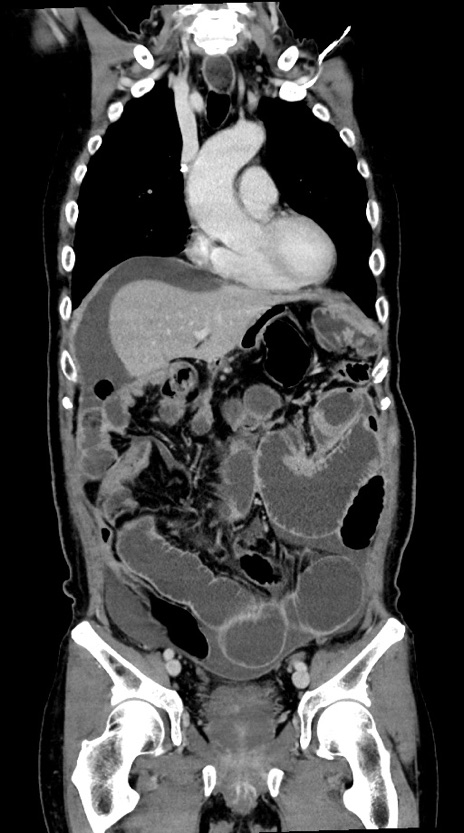

症例28(冠状断像)

【症例】60歳代男性

【主訴】嘔吐

【現病歴】胃癌にて胃全摘後。食思不振が悪化し、夜中に嘔吐することがある。

【既往歴】胃癌、胃全摘、脾摘、胆摘後

【データ】WBC 5900、CRP 10.56